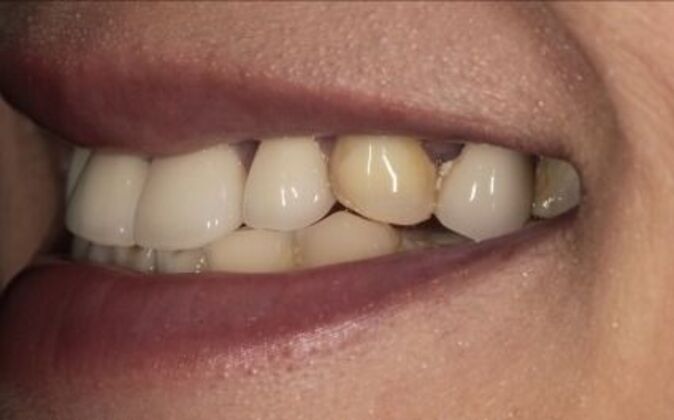

Full Mouth Reconstruction: Risa

Description

Full mouth reconstruction. When you see a client at a young age with so much dental work to begin with you consider your options carefully. You need to be aggressive in approach and conservative in maintaining as much of the healthy tooth structure. Have to consider the age of a patient whenever you embark on a major dental work especially when it involves redoing everything, repositioning and re-establishing a brand new bite position and correcting the inflammatory gum response from previous dental work. You cannot approach a case like this with a limited treatment plan that only addresses a few teeth. If this case is treated one tooth at a time you may leave the patient a “dental cripple”. By that I mean that this patient will constantly be at dental offices for the rest of her life addressing one broken down tooth after another until a cascading domino effect will render all the teeth in a hopeless condition. Here is a situation where we are dealing with multiple problems 1-bite collapse and malfunction 2-gum disease exacerbated by poorly fitting crowns 3-decaying teeth affecting the health of the roots This case had to consider all of these issues. Must understand that this patient is very young and has many years ahead of her so the dentistry has to be done meticulously, conservatively,aggressively and expeditiously. It’s a tough balancing act but as dentists we need to be realistic about our treatment objectives and have a proper plan that addresses dental breakdown. We were able to achieve the esthetic and functional concerns of the patient. Although we felt the color of the teeth were too bright. We do need to consider patients desires since they need to live with this for the rest of their lives and ultimately they need to be happy